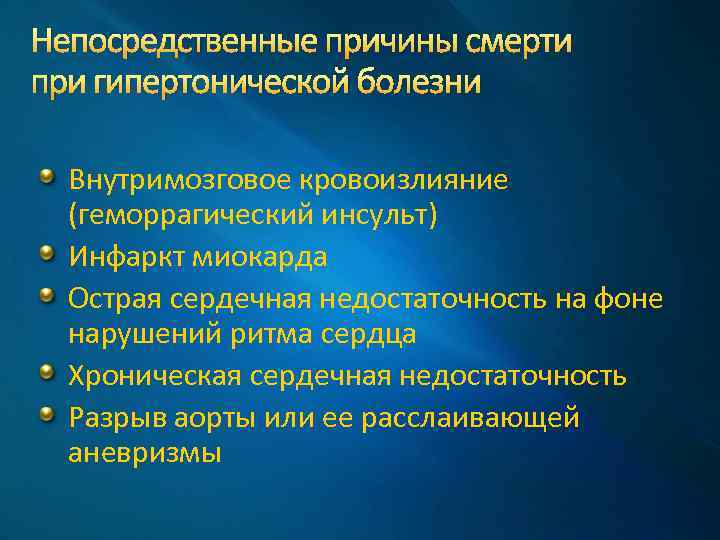

Непосредственные причины смерти при гипертонической болезни Внутримозговое кровоизлияние (геморрагический инсульт) Инфаркт миокарда Острая сердечная недостаточность на фоне нарушений ритма сердца Хроническая сердечная недостаточность Разрыв аорты или ее расслаивающей аневризмы